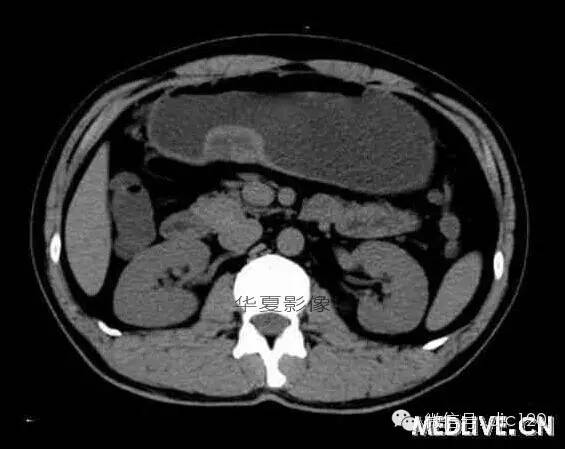

男,36歲,間斷性返酸噯氣3年,3個(gè)月前出現(xiàn)上腹疼痛,饑餓時(shí)加重。圖1-3為CT平掃,圖4-6分別為CT增強(qiáng)掃描的動(dòng)脈期、門脈期和延遲期。

CT檢查可見胃幽門前區(qū)胃小彎側(cè)胃壁局限性增厚、隆起或伴凸向胃腔內(nèi)的小結(jié)節(jié)灶,寬基地,境界光整,注射對(duì)比劑,增強(qiáng)掃描后,CT值可達(dá)50HU以上,與正常胰腺?gòu)?qiáng)化相仿。

胃迷走胰腺大多位在距幽門1-6cm的胃竇胃大彎側(cè),粘膜下層內(nèi),為1-3cm大小的病灶。 與胃壁以寬基底相,增強(qiáng)掃描病灶表面覆蓋的黏膜明顯強(qiáng)化且連續(xù),病灶內(nèi)無(wú)明顯壞死,病變強(qiáng)化方式類似于正常胰腺組織;當(dāng)病灶出現(xiàn)邊緣臍凹征或中央導(dǎo)管征時(shí),對(duì)EP的診斷具有一定的特異性。